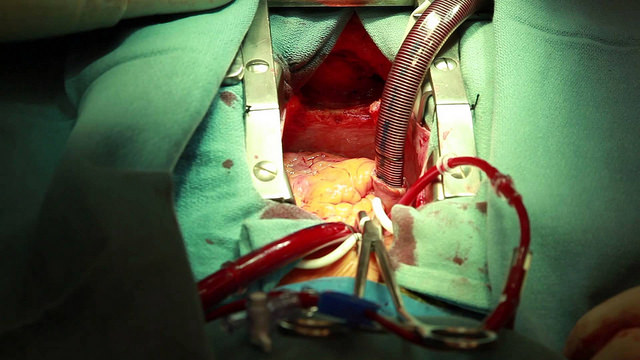

3) Death is often kinder – but that isn’t a decision you can necessarily make

‘Bitter experience of similar cases to Mr Williams’ told me that the best outcome for this man would be if the operation killed him – but I felt unable to let that happen. I knew of surgeons in the distant past who would have done just that, but we live in a different world now. At moments like this I hate my work.’

The sheer terror of having a severe brain injury is that you cannot make decisions about your own future. If you are unconscious or semi-conscious your family will make your decision for you – and often, they cannot bear to let you go, even if surviving means life on a ventilator in a vegetative state. Here lies Marsh’s tale of the evils of competitive modern medicine. As a surgeon, if you refuse to operate there will always be someone who will simply for profit and regardless of moral consequences. This could result in bad reviews, a resulting lack of patients, and your clinic closing down. Your hand is therefore forced – you are forced to create a living vegetable for families to be burdened with without much help, especially as in places without universal healthcare there will be little provided to help such families. Medicine to heal and medicine for profit is a fine tight-rope all doctors must walk on – however, with competing private hospitals and a culture of over-treatment, Marsh argues it is hard to stay balanced.